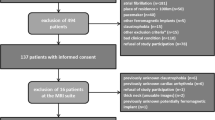

The study protocol was reviewed and approved by the local ethics committee and written informed consent was obtained. Twenty one patients who had a carotid stenosis of at least 40% on Duplex ultrasound using NASCET criteria [23] were recruited in total. Ten were symptomatic (nine males, mean age 72 years, range 59–86 years) with a recent history (less than 6 months) of transient ischemic attack (TIA), and 11 were asymptomatic (seven males, mean age 78 years, range 68–87 years).